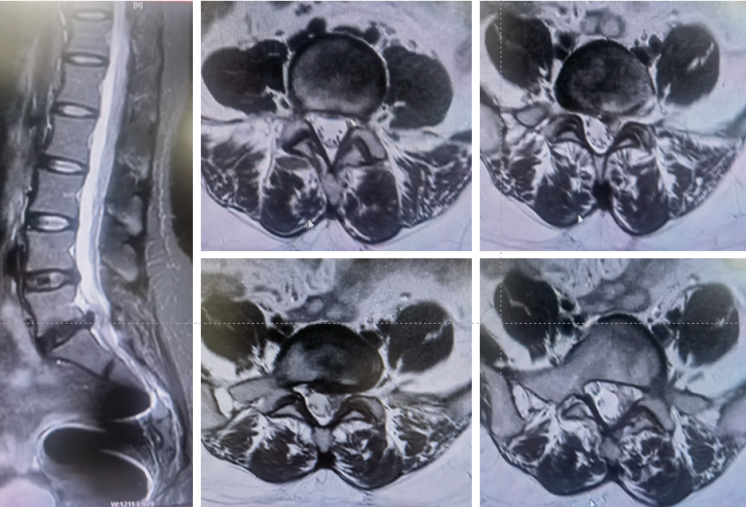

这次手术的主角是一位45岁的姐姐,她被“反复腰痛+左下肢放射性疼痛、麻木”困扰了4个月,实在遭不住才来医院。检查发现是L5-S1腰椎间盘突出,神经遭压得梆紧,保守治疗根本不管用,连日常走路、上班都成了难题。传统手术虽然能解决问题,但“大刀阔斧”的创伤和漫长的恢复期想想就脑壳痛!为了让姐姐少受罪、快康复,咱们多学科团队反复评估后,决定用国际前沿的PEID微创手术“精准打击”!